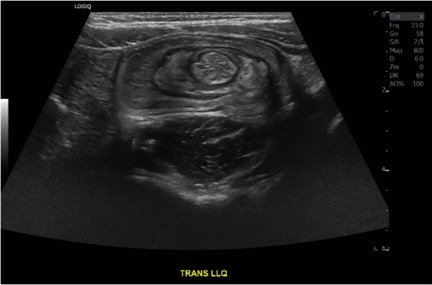

Case Report of a Child with Colocolic Intussusception with a Primary Lead Point

DOI: https://doi.org/10.21980/J8564QOn the initial ED visit, an abdominal ultrasound (US) was ordered which showed the classic intussusception finding of a target sign (yellow arrow), or concentric rings of telescoped bowel, on the transverse view of the left lower quadrant (LLQ).